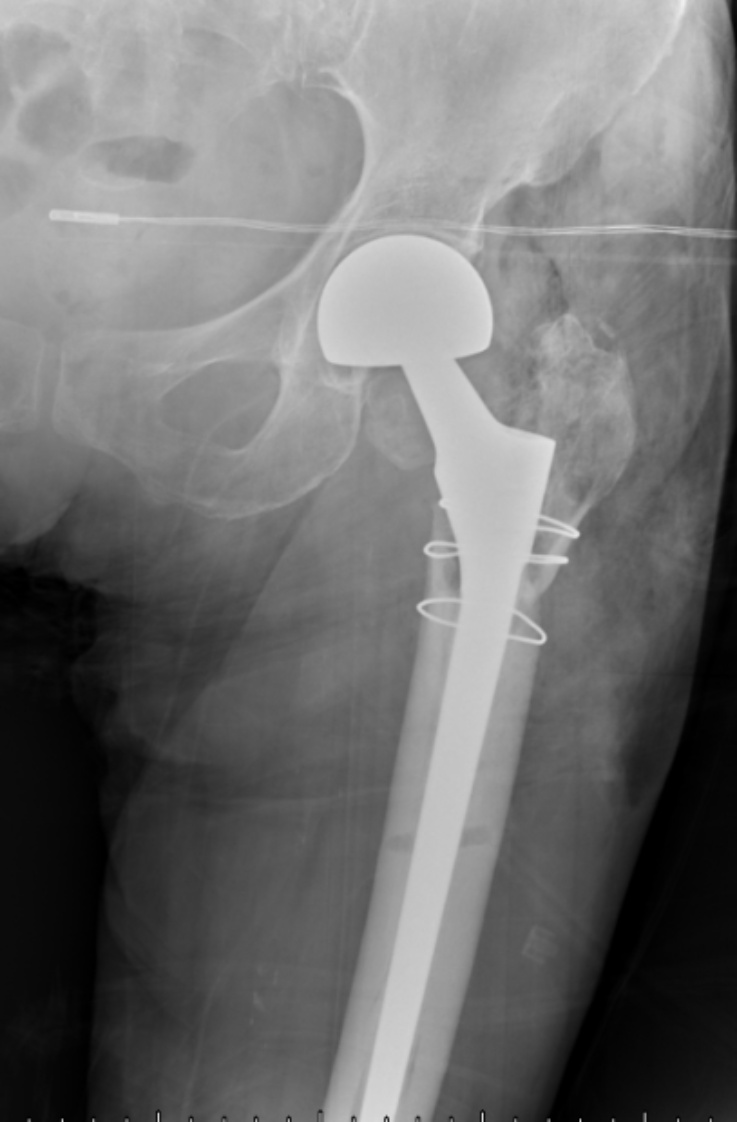

典型病例影像学表现见图1~10。图1为86岁女性右侧股骨转子间骨折(Evans Ⅲ型)患者,术前X线示骨折断端部分错位,术后X线示骨折位置可以及假体位置良好;图2显示了一名81岁男性患者,诊断为左侧股骨转子间骨折,类型为Evans V型,合并股骨干陈旧性骨折。患者接受了生物型加长柄半髋关节置换手术,并进行了股骨近端的钢丝捆扎内固定。术后X线示假体位置良好,股骨近端予钢丝捆扎固定;图3为87岁女性左侧股骨转子间骨折(Evans V型)患者,术后X线示假体位置良好,股骨大小转子骨折位置可,钢丝捆扎固定在位有效;图4为75岁女性左侧股骨转子间骨折(Evans V型)患者,术前X线示左侧股骨转子间骨折PFNA术后、骨折未愈合、内固定断裂。术后假体匹配良好,股骨近端钢丝内固定稳定可靠;图5为75岁男性左侧股骨转子间骨折(Evans IV型)患者,术后股骨大转子出现轻度位移,假体位置正常。图6为87岁男性左侧股骨转子间骨折(Evans V型)患者,给予DAA入路加长柄半髋关节置换,术前X线片,清晰地显示出左侧股骨转子间的骨折情况,术后X线影像,显示股骨的大小转子骨折位置良好,钢丝内固定装置在位稳定,假体位置良好;图7为77岁女性右侧股骨转子间骨折(Evans V型)患者,术前X线片显示右侧股骨转子间存在骨折且股骨大小转子均有累及和移位,术后X线片显示股骨小转子轻度移位,内固定装置位置稳定,假体位置良好;图8为70岁男性左侧股骨转子间骨折(Evans III型)患者,术前的X线片,清晰地显示了左侧股骨转子间的骨折情况,股骨近端髓腔钙化灶,术后假体位置满意;图9为77岁女性右侧股骨转子间骨折(Evans V型)患者,术前X线片,显示右侧股骨转子间及转子下部位骨折情况。术后假体匹配良好;图10为71岁男性右侧股骨颈骨折(Evans IV型)患者,术前X线片,显示右股骨转子间骨折的情况;术后X线表明股骨的大转子和小转子骨折位置保持良好,内固定装置稳固,术后假体位置正常。

Figure 2. An 81-year-old male patient with left intertrochanteric fracture of the femur (Evans type IV). (a) Before surgery; (b) After surgery

2. 81岁男性左侧股骨转子间骨折(Evans Ⅳ型)患者。(a) 术前;(b) 术后